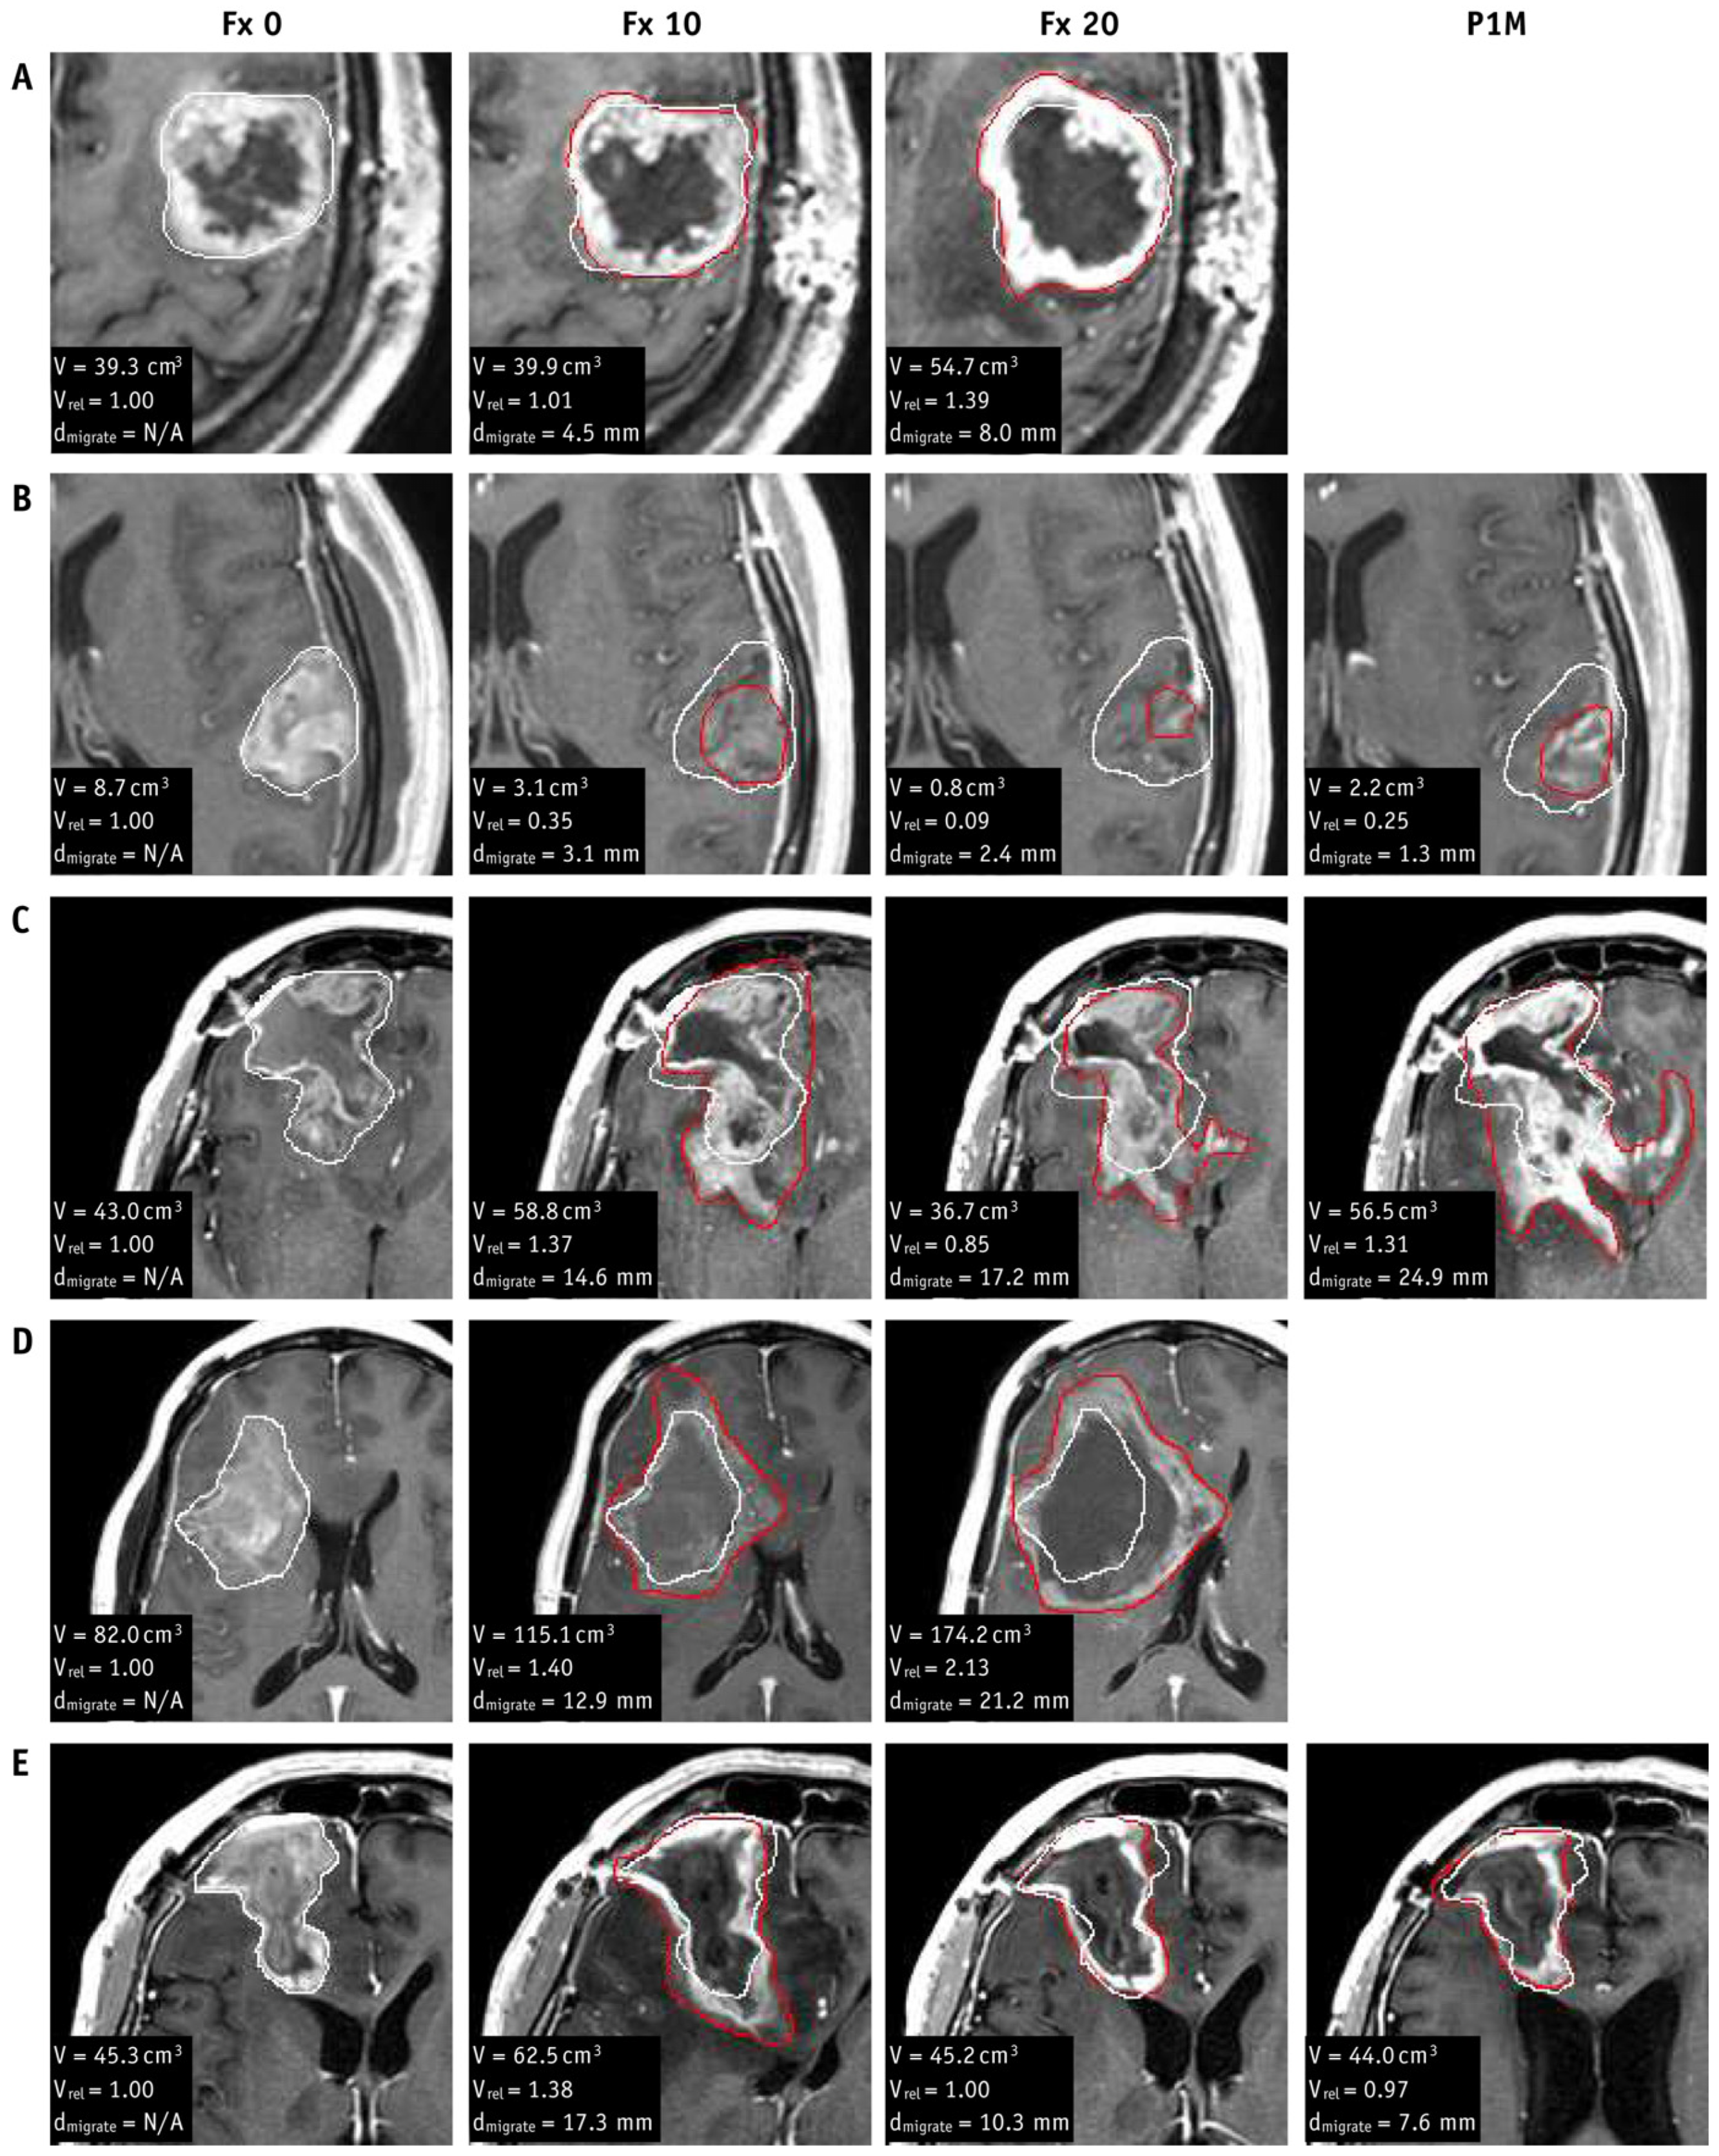

There are two limitations of the current radiotherapy strategies for gliomas that will be of relevance later in this review. First, gliomas can change substantially during the three to six weeks of radiation treatment [26,27], but the treatment plan is typically kept unchanged from pre-radiotherapy or is adapted only once. See Figure 1 for examples of changes that can occur in glioblastomas during radiotherapy. Adaptation to ensure tumor coverage may be necessary, especially in the era of small-margin radiotherapy to attempt to spare normal brain toxicity [28,29]. Second, radiotherapy targets are based solely on T1- and T2-weighted imaging, but enhancing tumor is only reflective of tumor that has disrupted the blood–brain barrier, while T2-weighted imaging hyperintensities have a mixture of infiltrating tumor and edema that is difficult to distinguish [21]. Gliomas are spatially heterogeneous in oncogenic signaling, proliferation, and hypoxia [30,31], which renders some regions of the tumor more aggressive or prone to relapse than others. This heterogeneity is not considered for treatment planning.

Figure 1.

Glioblastomas can change rapidly during treatment. Zoomed images of contrast-enhanced T1-weighted MRI for five cases of glioblastomas (A–E) at treatment planning (Fx 0), fractions 10 and 20 (Fx 10 and Fx 20), and one-month post-radiotherapy (P1M). The white contour shows the gross tumor volume (GTV) at planning while the red contour shows the GTV at the specified timepoint. The absolute volume (V), the volume relative to planning (Vrel), and the maximum distance of the new GTV from the planning GTV (dmigrate) are listed in the lower left-hand corner of each image. Figure was reproduced from Stewart et al. with permission from the publisher [26].